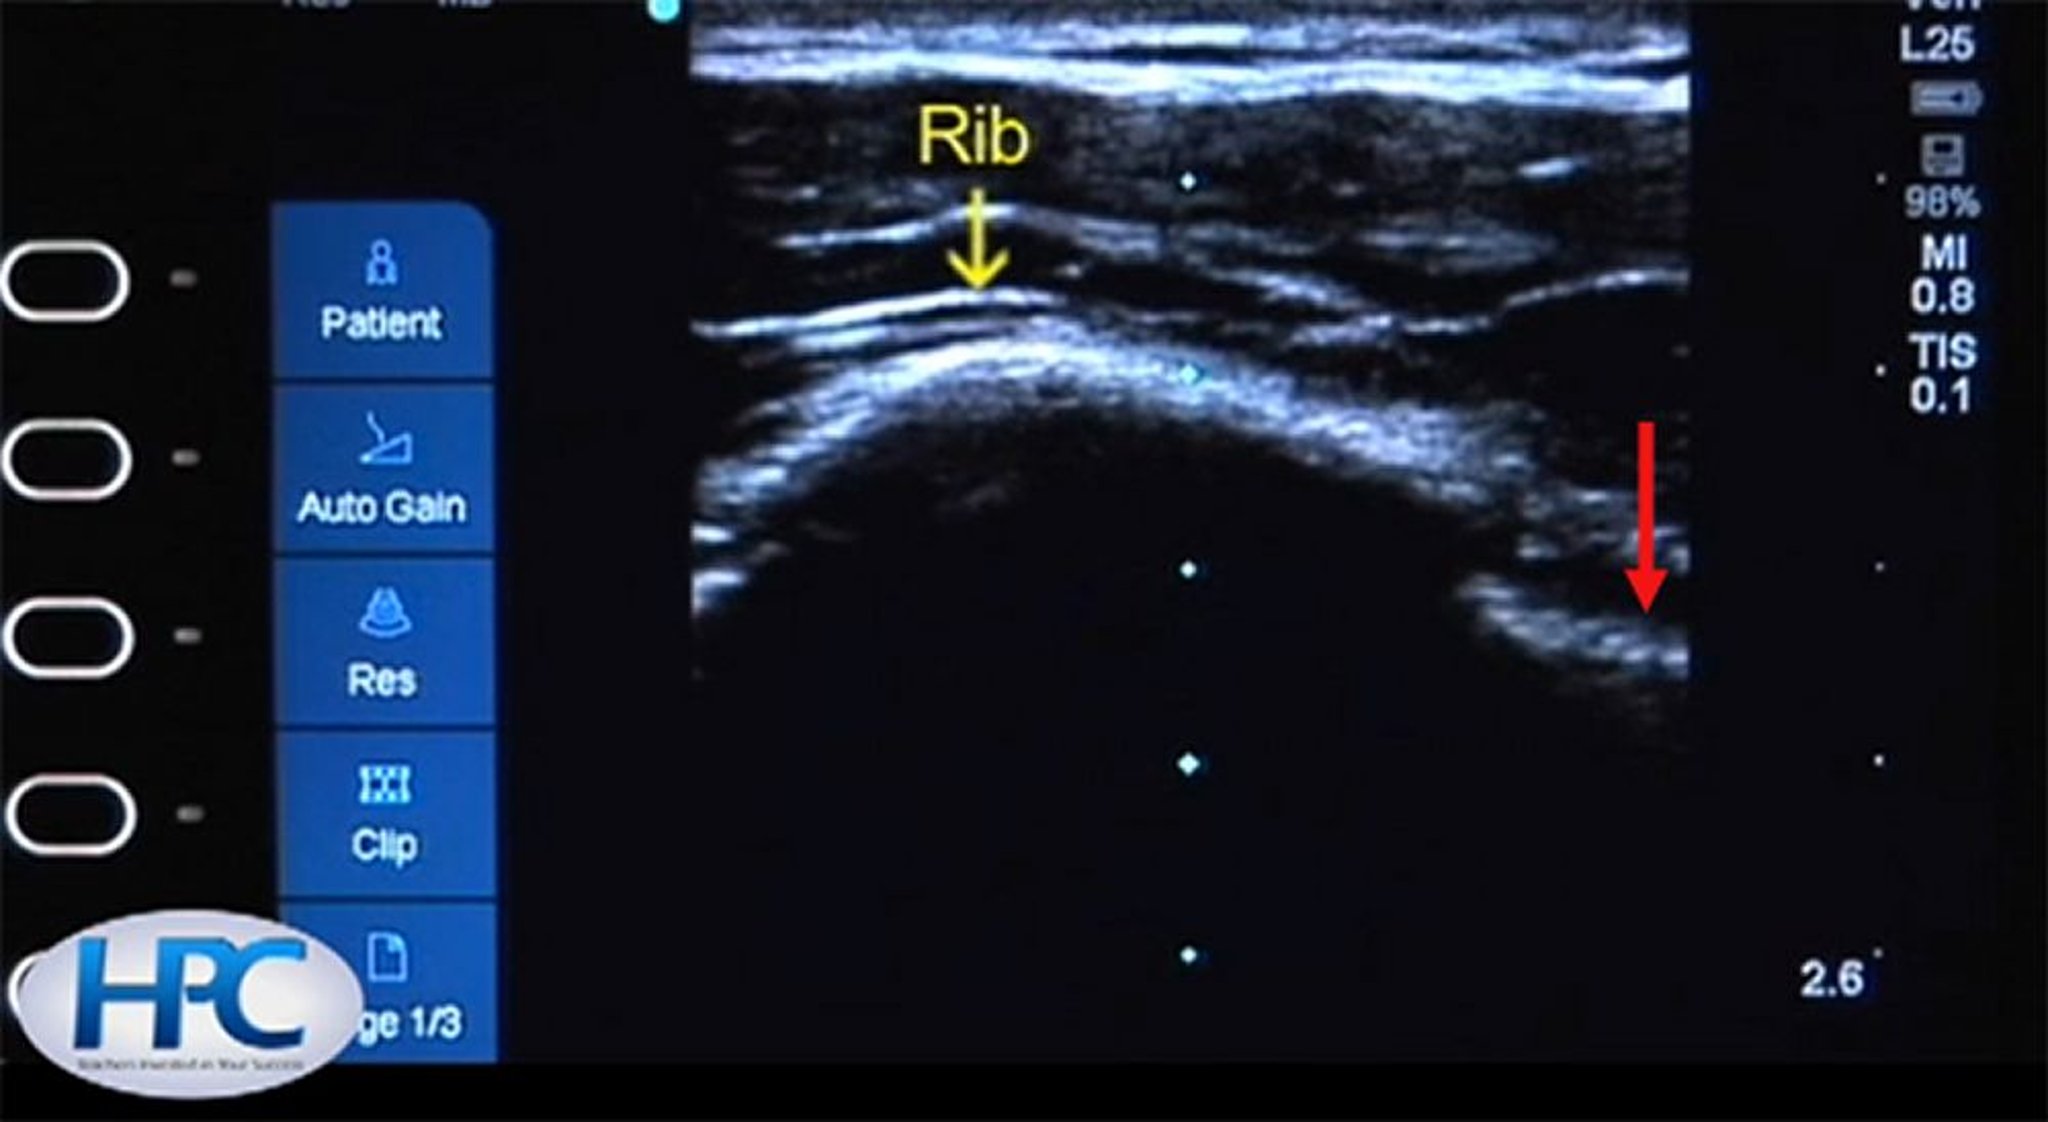

Aparência ultrassonográfica dos arcos costais e da linha pleural

O arco costal (flecha amarela) aparece como uma estrutura hiperecoica (branca) com sombreamento abaixo do arco costal. A linha pleural (flecha vermelha) é visível no espaço intercostal.